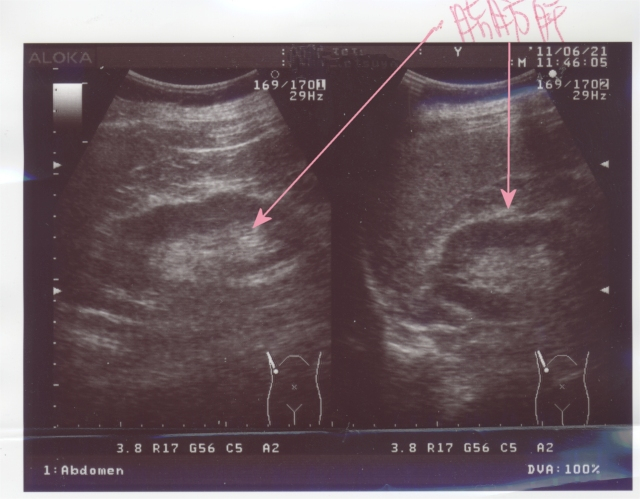

で、ついでに腹部エコー検査。

肝臓っす。

相変わらず、脂肪肝だった。

初~中軽度だって。coldsweats01

画像の矢印の白いのが脂肪肝。

そろそろ、フォアグラ状態でrestaurant食べごろかな。delicious

脂肪肝も薬じゃ治らないから、運動と食事で治すしかないって。despair